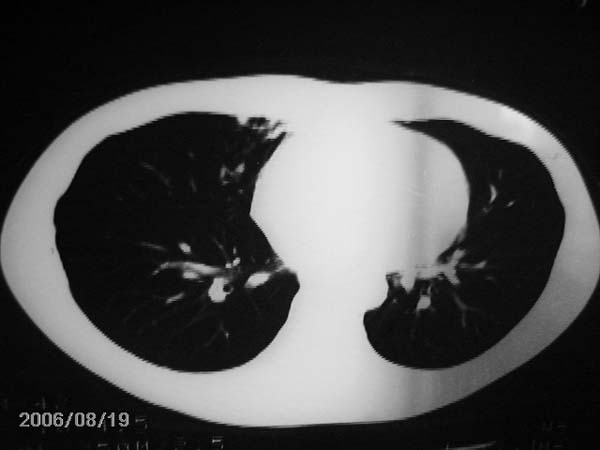

男,13岁,发烧半月,干咳无痰,正规使用抗生素半月,现在仍是午后低烧!!!未做痰检

结合临床考虑:右肺中叶结核可能性大.

右肺中叶结核可能性大

右肺结核,右肺中叶不张

右侧肺门淋巴结好象有增大,会不会是个原发综合症合并感染

右中肺呈大片状密度欠均匀影,内见含气支气管.

结合病史,考虑:右中肺大叶性肺炎(吸收期).

右肺中叶大片状密度增高影,内密度不均匀,右肺门处增大,应该是淋巴结肿大,结合临床首先考虑原发性肺结合可能性大,不排除合并感染可能,建议治疗后复查.